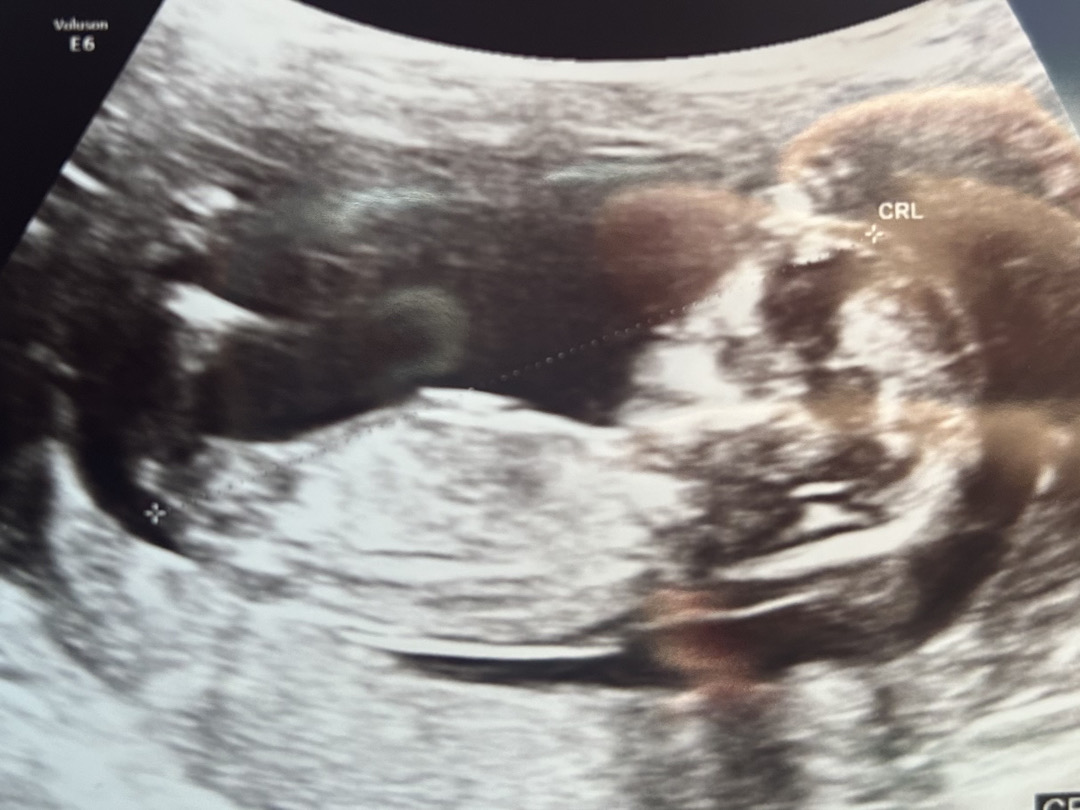

각도법 좀 봐주세요ㅠㅠ 간절합니다ㅠㅠ

12주4일 촘파에요!!! 아들일지 딸일지 너무 궁금해요ㅠ 투표 한번씩만 해즈세요오ㅠ